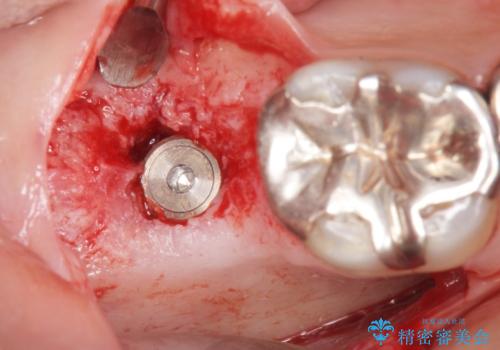

レントゲン及びCTを撮影し骨の状態を確認したのち、アルファタイトインプラントによる治療を行いました。

インプラントの種類:アルファタイト

- 外科手術のため、術後に痛みや腫れ、違和感を伴います